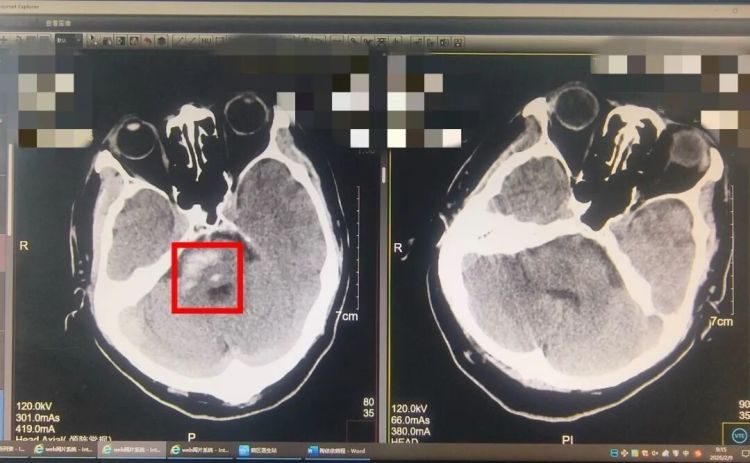

头颅CT结果显示:脑干出血。

脑干

是人体的“生命中枢”,呼吸、心跳、意识全由它掌控。哪怕几毫升的出血,都可能致命。